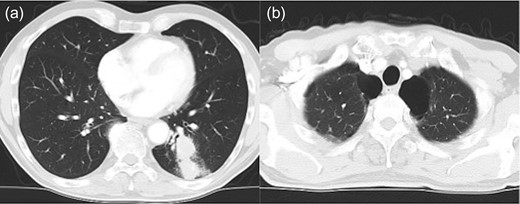

Left lower lobectomy and lymph node dissection were performed. Preoperative computed tomography imaging revealed multiple bullae in the apex of the left lung and very thin bullae walls (Fig. 2A). Concerned that the patient would develop a second primary lung cancer or pneumothorax in the future, we simultaneously performed a bullectomy for two bullae with a lobectomy (Fig. 2B). Because the patient’s lung was highly emphysematous, linear staplers with PGA felt (Endo GIA™ Reinforced Reload with Tri-Staple™ Technology, cartridge color: purple, MEDTRONIC, Tokyo, Japan) were used for the bullectomy. We confirmed the absence of bleeding in the thoracic cavity and completed the operation (Video 1). The drainage from the thoracic tube turned bloody beginning 1 h after the operation. The drainage volume increased, and 600 ml of bodily drainage was observed for 2 h after the drainage had turned bloody. A chest X-ray imaging examination was performed, which confirmed fluid accumulation in the left thoracic cavity (Fig. 3). Because the patient’s anemia had also progressed, as compared with preoperative measurements (preoperative hemoglobin, 12.8 g/dl; 3-h postoperative hemoglobin, 9.1 g/dl), we determined that sustained bleeding had occurred in the thoracic cavity; we subsequently decided to carry out a reoperation to perform hemostasis. No air leakage was observed during the period between both operations.

The bulla (*) wall in the apex of the lung was very thin (a). Following left lower lobectomy, the resection of emphysematous bullae (*) was performed (b).